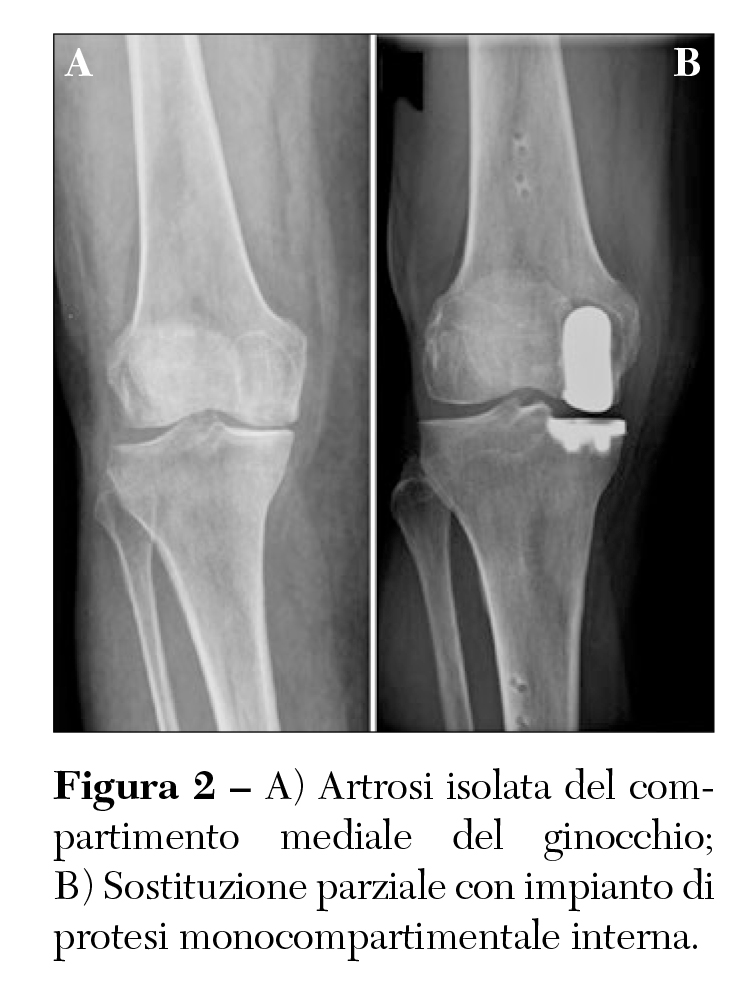

Esistono tuttavia delle forme, non necessariamente meno lievi come sintomatologia dolorosa, in cui però solo una parte (compartimento) del ginocchio è usurata e per cui è possibile eseguire un intervento meno invasivo andando a sostituire soltanto la parte usurata con una protesi parziale o monocompartimentale (Figura 2).